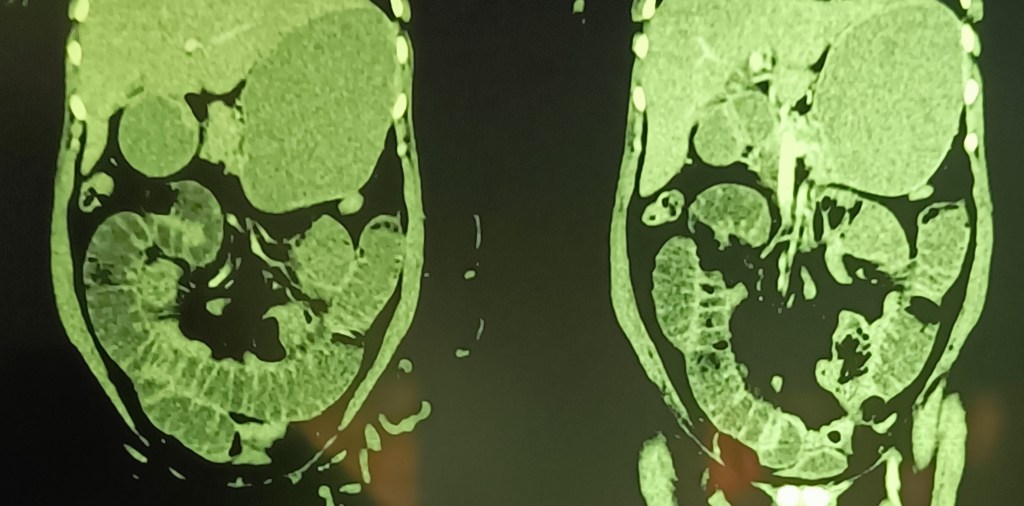

A 66-year-old female was admitted on 6.12.24 with severe abdominal pain and some distension. X-ray showed multiple air-fluid levels.

CT scan the next day showed SBO at mid-level.

Soon after the CT, the patient’s condition had rapidly improved, with resolution of all symptoms. Neither the patient nor her consultant physician wanted surgery, and so had to withhold the knife, and the patient was discharged.